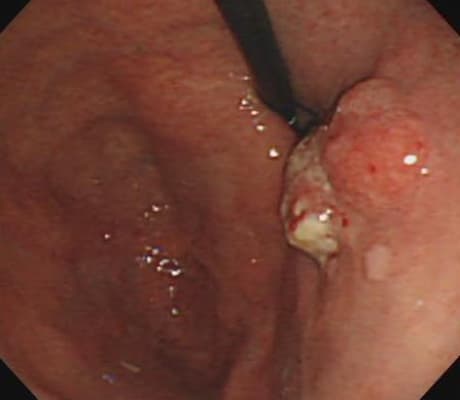

先端の太さが5.4㎜で、鉛筆と同程度の非常に細い胃カメラで検査を行っておりますので、苦痛なく検査が行えます。通常の観察に加え、NBIという技術を用いた特殊光観察を行うことができます。NBIとはNarrow Band Imaging (狭帯域光観察)の略で、特殊な光を使って粘膜表面を色調を変えて観察することにより、がんの早期発見や炎症などの他の原因との鑑別診断に役立ちます。